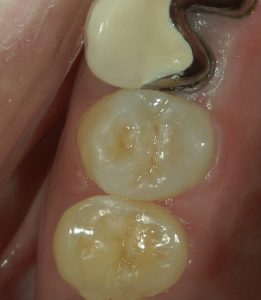

治療前の写真です。

銀歯を除去すると中はむし歯により傷んでいました。

銀歯での治療ではこのようにむし歯が再発・進行しやすい環境であるため短い期間で再治療が必要となり、更に神経を失うリスクが高まってしまいます。

上の写真では下に位置する隣の歯に、侵襲・ダメージを最小限に抑えるためダイレクトボンディングを行っています。

上の写真では神経近くまでむし歯が進行していたため、このMTA系神経保護材を用い歯髄(歯の神経)保存治療を行なっています。